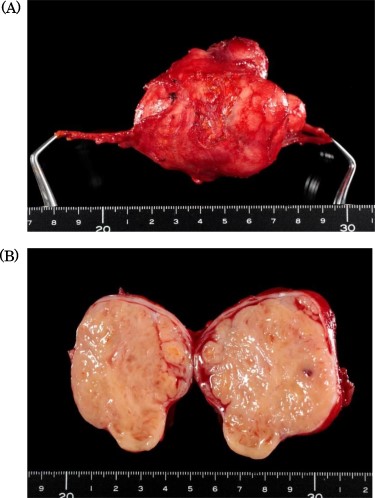

Specimen showed a solid tumor with white color, 80 × 40 mm in diameter.

Intraoperatively, the tumor was located in the right retroperitoneal space and did neither adhere to nor invade other organs. The right ovarian vein ran cranially to caudally through the tumor. A central tumor thrombosis was detected in the ovarian vein (Fig. 5). We performed the resection of the tumor together with the right ovarian vein. The specimen showed a grayish-white solid tumor with the ovarian vein passing through its center (Fig. 6). Microscopically, fascicular hyperplasia of eosinophilic spindle cells with high-grade dysplasia and atypical mitotic figures were detected. Elastic fibers of the vessel wall were identified in the tumor. Immunostaining revealed that the tumor was positive for smooth muscle actin and desmin and negative for s-100 protein and c-kit. Based on these findings, our diagnosis was a LMS arising from the ovarian vein (Fig. 7). The immediate postoperative course was uneventful and the patient was discharged on day 11 postoperatively. Five months after the surgery, multiple lung metastases were detected on CT and chemotherapy was initiated (doxorubicin + olaratumab).